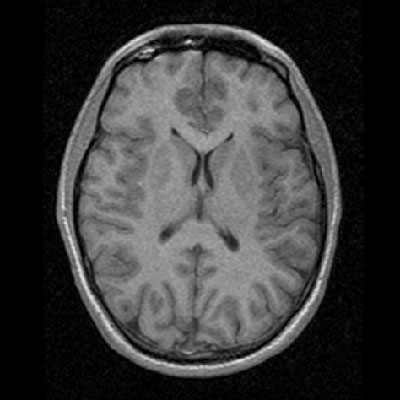

A sagittal T1-weighted magnetic resonance image of my head, highlighting my corpus callosum and brainstem An axial T1-weighted MR slice showing my basal ganglia and frontal and parietal lobes

An axial T1-weighted MR slice showing my basal ganglia and frontal and parietal lobes